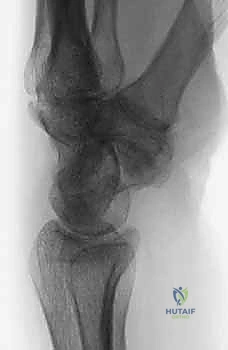

متلازمة SNAC (Scaphoid Nonunion Advanced Collapse) هي حالة تدهور تدريجي ومأساوي لمفصل الرسغ. تبدأ القصة بكسر في العظم الزورقي (غالباً بسبب السقوط على يد ممدودة). إذا لم يتم تشخيص هذا الكسر أو لم يلتئم بشكل صحيح، فإن العظم الزورقي ينقسم إلى قطعتين تتحركان بشكل غير طبيعي ومستقل عن بعضهما البعض.

هذه الحركة غير الطبيعية تخلق احتكاكاً مستمراً (Micro-trauma) مع العظام المجاورة، وتحديداً عظم الكعبرة (Radius). بمرور الوقت (أشهر أو سنوات)، يؤدي هذا الاحتكاك إلى تآكل الغضاريف الناعمة التي تغطي العظام، مما يسبب خشونة مفصلية شديدة (Osteoarthritis).

مراحل تطور متلازمة SNAC:

- المرحلة الأولى (Stage I): خشونة وتآكل في المفصل بين القطب البعيد للعظم الزورقي وعظم الكعبرة (الناتئ الإبري الكعبري).

- المرحلة الثانية (Stage II): يمتد التآكل والخشونة ليشمل المفصل الزورقي الكبير (Scaphocapitate joint).

- المرحلة الثالثة (Stage III): تدهور كامل يشمل المفصل بين عظم الهلالي والعظم الكبير (Capitolunate joint)، مع انهيار كامل لهيكل الرسغ.